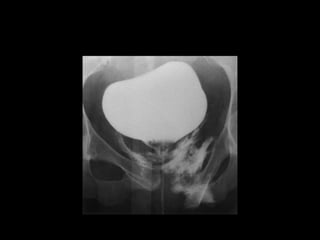

Diagnostico

• Estudio elección: cistograma de llenado 350-

400ml solución salina, con 4% de contraste a

una altura de infusión de 40 cm.

• Cystography: Gold standard

• CT Cystography : New trend

• Peng et al. AJR 2011.

– Prospective study

– 305 patients.

– Cystography VS. CT cystography

– Ruptures confirmed by Surgery

– 100% sensitive and specific